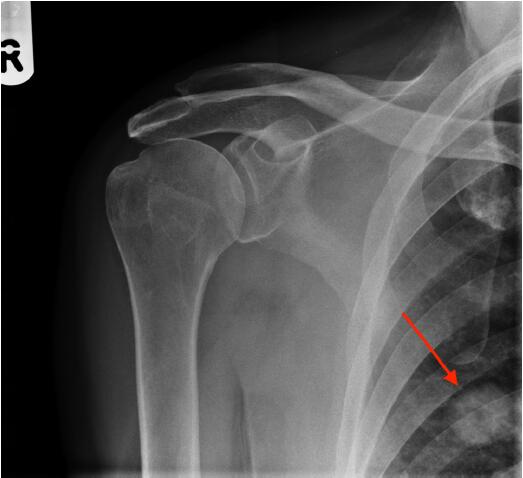

圖2肩X光片顯示一空洞性肺結(jié)節(jié),約2cm。很可能是原發(fā)性肺癌,需要轉(zhuǎn)診至肺癌多學(xué)科小組。

圖2右肩前位X光平片,紅色箭頭指示一空洞性肺結(jié)節(jié)

該例患者接受了胸部和腹部CT掃描,隨后取了活檢,證實(shí)為T2N0M0原發(fā)性肺腺癌。對(duì)給患者予以手術(shù)切除,2年隨訪時(shí)仍無(wú)病。